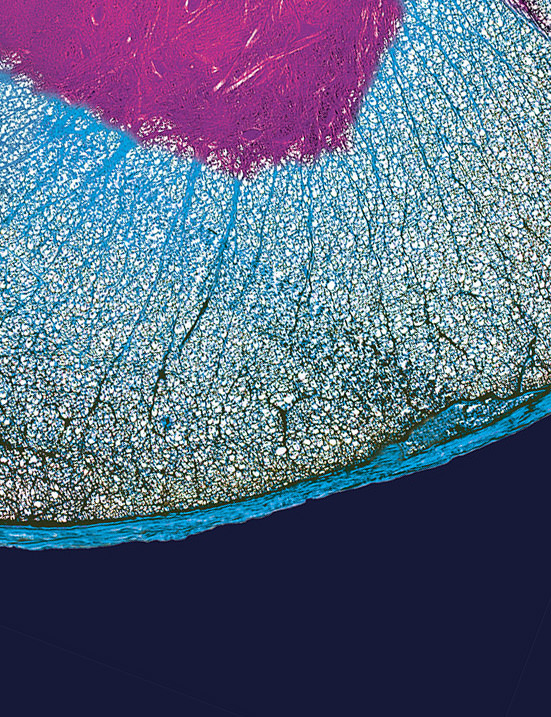

Mieux comprendre et mieux traiter les démences – dont celle conséquente à la maladie d’Alzheimer – qui touchent plus de 57 millions de personnes dans le monde. Grâce à l’IA, le projet a pour objectif d’identifier les mécanismes à l’origine de la démence associée à une atteinte des petits vaisseaux du cerveau, et identifier de nouveaux biomarqueurs du déclin cognitif.

L’équipe des Prs. Stéphanie Debette et Hugues Chabriat analyse conjointement des données génétiques, moléculaires et cellulaires et d’imagerie cérébrale de patients dont la dégénérescence neuronale à composante vasculaire est avérée.

Identifier les mécanismes vasculaires associés à la neurodégénérescence et qui mènent à l’état de démence, pourrait faire émerger de nouvelles thérapies pour freiner l’évolution des symptômes et prolonger la qualité de vie des patients.